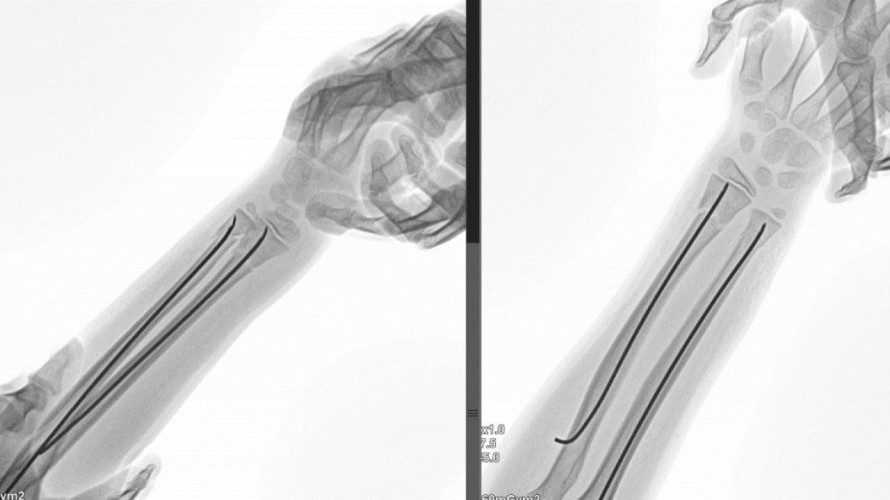

Новый способ лечения переломов запястья у детей разработали хирурги из Иркутска и Санкт-Петербурга

Методика сократила число осложнений на 80%, а время ношения гипса — на неделю

Врачи Ивано-Матрёнинской детской клинической больницы в Иркутске совместно с коллегами из Национального медицинского исследовательского центра травматологии и ортопедии имени Г.И. Турнера в Санкт-Петербурге разработали и внедрили новый метод хирургического лечения одной из самых частых детских травм — перелома лучевой кости в области запястья.